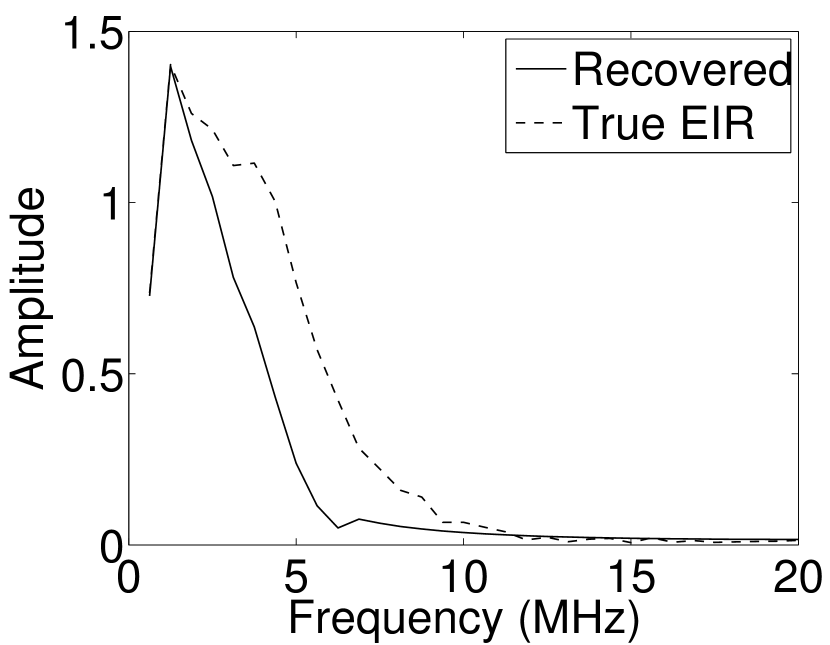

Figure 7(a) reveals that use of the inaccurate EIR in the conventional iterative method created strong artifacts and distortions. Figures 7(b) confirms that the artifacts and distortions were significantly mitigated when the VP method was employed. Image profiles for both cases are shown in Figures 7(c). The overall accuracy of the recovered EIR, shown in Figure 7(d) and 7(e), was improved, but it contained spurious oscillations.